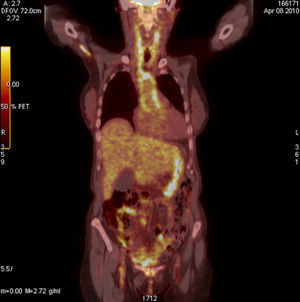

Case 2This case was a 74-year-old woman with pain and weakness of the shoulders and hips, with morning stiffness of more than 1h and elevated acute phase reactants. Suspecting polymyalgia rheumatica (PR) we administered 30mg/day of prednisone with initial improvement, but rapid recurrence of symptoms and deterioration in the laboratory tests, with a hemoglobin of 8mg/dl, CRP 19mg/dl and an ESR of 120mm in the first hour. The patient reported no headache, jaw claudication or tenderness on the temporal artery and peripheral pulses were normal. Suspecting a neoplasia we requested tumor markers, a thoracoabdominal CT, gastroscopy and colonoscopy, all with normal results; the study was completed, finally, with the performance of a PET-CT (Fig. 2) which evidenced a vasculitic process in the Ao, innominate, carotid and subclavian arteries. Given the strong suspicion of GCA we performed a temporal artery biops, which confirmed the diagnosis.